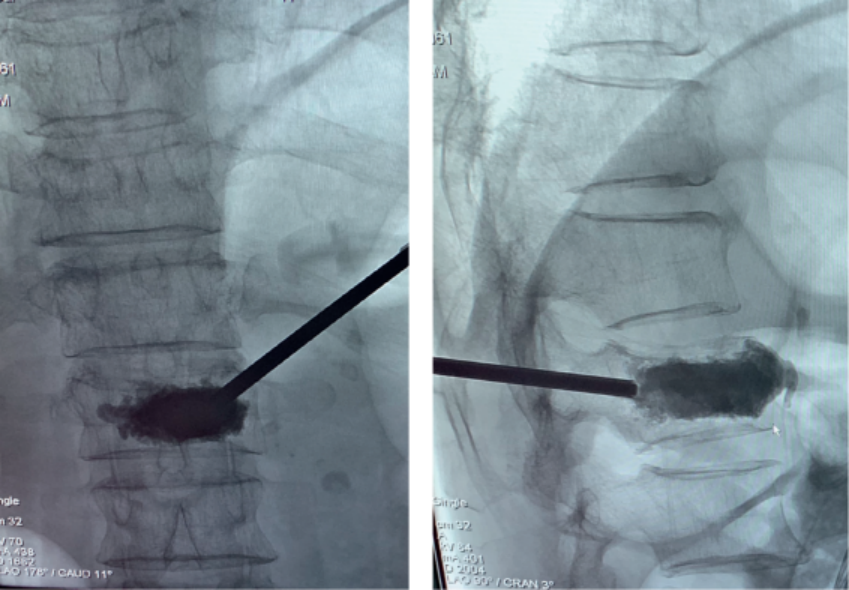

椎体成形术(PVP):

经皮椎体成形术(percutaneous vertebroplasty,PVP)是经皮由椎弓根置入,骨水泥注入椎体,从力学上增强其结构强度。

椎体成形术(PVP)病例